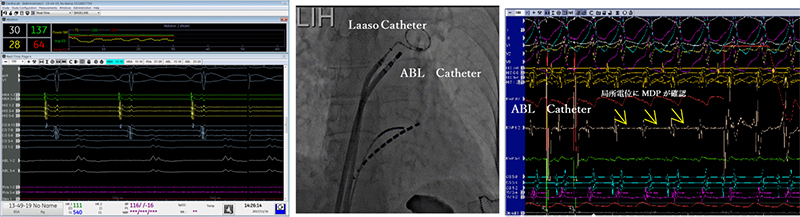

Prucka_tsukuba_04.jpg

CardioLabシステムは最大224極112chの心内電位を含む128chのレコーディング機能や各社のアブレーション装置、心臓刺激装置ならびに3Dマッピング装置とのCARTOインターフェイス機能等、ハイエンドのアブレーション治療支援に要求される機能を備えたシステムである。当院でCardioLabシステムを使用する際、カテーテルアブレーション・植込みデバイス治療で使用している。本装置に搭載されているカーディオICEインターフェイスはCardioLabシステムの画面に超音波診断装置(Vivid-i・S-70)のリアル画像を取り込むことができる。当院では主に穿刺時や肺静脈隔離術(PVI)、心室頻拍症例(VT)においてを超音波診断装置(Vivid-i・S-70)のリアル画像心房中隔穿刺(Brockenbrough)時にLabシステムの画面に表示させ使用している。

Prucka_tsukuba_05.jpg

また、CardioLabシステムと3Dマッピング装置を連携することができる機能は3Dマッピングで取得したマッピングポイントの位置や電位取得情報、アブレーションしたポイントをラボシステムに反映することができる機能である。

Prucka_tsukuba_06.jpg

Prucka_tsukuba_07.jpg

当院ではこの機能を活用し、必ず治療前にラボシステムの時間と3Dマッピング装置の時間を合わせて取り組んでいる。特に心室頻拍(VT)症例においては異常電位(遅延電位・破砕電位)が治療戦略において極めて重要でラボシステムと3Dマッピング装置を連携することで症例中にも重要な電位情報を確認することができるため有用な機能の一つである。さらに前述で述べた通り、本装置はアブレーション通電時に透視画像(正面・側面)を同時にImage Captureされ、症例後の解析にアブレーションのカテーテル焼灼部位の位置や通電情報、3Dマッピングポイントの電位情報やアブレーションポイントが一致するので当院では必要不可欠な機能であると考えている。